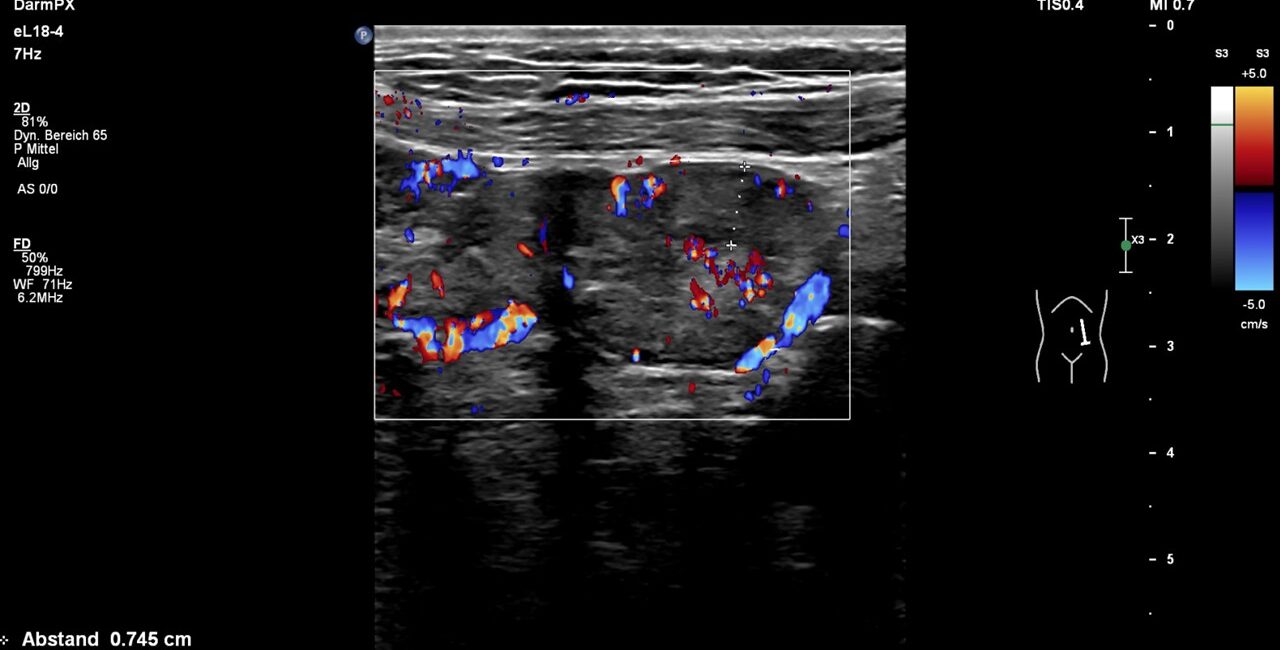

While changing body posture , the perfusion of the hyperperfused small bowel changed rapidly. To investigate this further, the venous and arterial perfusion of the small bowel was examined. There was no compromise to the superior mesenteric artery.

The flow volume quantification however led to an impressive finding. The superior mesenteric venous flow volume dropped from 889 mL/min while lying horizontally to 444 mL/min while standing.

Posture dependent flow volume changes in the superior mesentric vein and synchronously with similar extent in the jejunal wall

The ratio of the change in mesenteric venous flow volume in response to posture is reflected by a synchronous reduction in jejunal perfusion in the left paraumbilical region. Since a clear synchronicity was observed between the changing intensity of pain, the change in posture and the change in jejunal perfusion on the left side of the umbilicus, the exact location of the pain, it is concluded that swelling of the jejunum wall is a result of bowel congestion.

The PixelFlux perfusion measurement of the jejunal wall revealed a decrease of the perfusion by 43% after assuming an upright posture (see image above). The extent of the perfusion change of the jejunal wall was in the same range as the change of the flow volume of the superior mesenteric vein.